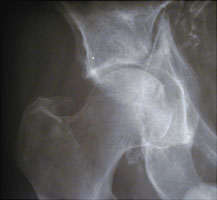

The name dashboard fracture refers to a fracture which typically occurs in automobile accidents with impaction of the knee upon the dashboard. This results in fracture of the posterior rim of the acetabulum by the femoral head.. This type of fracture is associated with patellar fractures and posterior cruciate ligament fractures.

- Click on the image for a larger versionAAP radiograph of the right hip. This shows a markedly comminuted fracture of the acetabulum, involving both the anterior and posterior columns. This patient was the driver of an automobile.